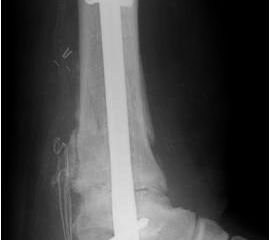

• Primäre oder posttraumatische Arthrose des OSG und USG (Abbildung 1, Abbildung 2).

• Revision einer gescheiterten Fusion des OSG/ USG (Abbildung 3, Abbildung 4).